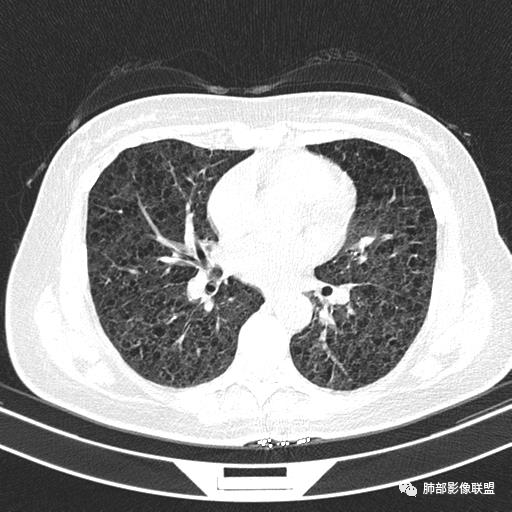

中年女性,不吸烟

双肺弥漫囊腔,累及肋膈角,囊腔形态相对规则单一。

CT平扫示双肺弥漫分布大小不等囊状薄壁透光区,无内、中、外带分布差异,间质稍示增厚。拟LAM

中年女性育龄期妇女,咳嗽气喘,无吸烟史,有苯吸入史。影像:双肺弥漫均匀小囊腔,无明显分布优势,囊腔形态欠规则,壁薄,部分囊腔边缘血管征,伴双肺弥漫磨玻璃影,无结节,考虑lam,鉴别苯中毒肺损伤,囊腔多有分布优势,小叶中心分布为主,形态规整等

女,46,活动性气喘1年。苯吸入史半年。胸部CT:两肺弥漫囊腔,上至肺尖,下至肋膈角,形态类似小囊腔。考虑:LAM,鉴别LIP,BHD,PLCH等。

双肺弥漫大小不一薄壁含气囊腔,囊间肺组织正常,正常肺背景,肺尖肺底受累;青年女性,气喘,支持LAM

CT表现:双肺弥漫大小不等的薄壁囊腔,囊壁<2mm,外形规则,血管影多位于囊腔周围,囊腔之间肺组织正常,随着疾病进展到晚期,囊腔变大、增多,不可胜数,囊腔可融合成较大的囊,与肺气肿相似,形成间质性肺纤维化。部分病例可出现结节影。